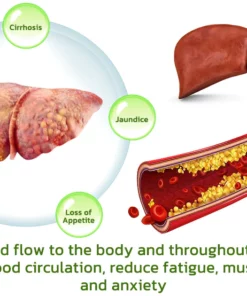

Dr. Shinichiro Hanada’s research team has created the BLUESKY Liver Care Patches, cleverly formulated with a pure herbal blend of vegan ingredients. Within 8 weeks, these patches work to repair the liver and restore its normal function, enhancing the body’s detoxification abilities. Additionally, they may help reduce excessive liver fat and promote the regeneration of new liver cells.

These substances are absorbed into the bloodstream through the capillaries of the skin and then act on the liver, enhancing detoxification and liver tissue regeneration. Compared to conventional liver cleansing treatments, this method is 25% more effective in liver detoxification and regeneration than pharmaceutical treatments.